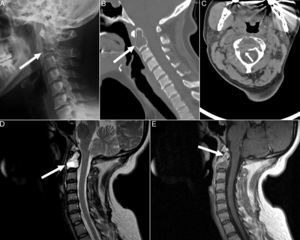

Radiografía lateral de columna cervical (A) en la que se observa una lesión osteolítica expansiva en el cuerpo vertebral de C2 con insuflación de la cortical (flecha). Cortes sagital (B) y axial (C) de la TC de columna cervical en la que se evidencia que dicha lesión reemplaza globalmente la médula ósea (flecha) y rompe la cortical en la superficie posterolateral derecha del cuerpo vertebral (flecha). Cortes sagitales en las secuencias potenciadas en T2 (D) y T1-posgadolinio (E) de la RM de columna cervical que muestra una zona quística, necrosis y trabeculación. La lesión es marcadamente hiperintensa en T2 e hipointensa en T1, mostrando realce periférico tras la administración de gadolinio (flechas).

Una paciente de 43años previamente sana consultó por dolor punzante en regiones occipital y cervical con parestesias asociadas en regiones suboccipital y retroauricular izquierdas (dermatomas C2-C3) de 9 meses de evolución. Recibió tratamiento con analgésicos, relajantes musculares y electroestimulación transcutánea sin notar mejoría. A la exploración presentaba limitación global de la movilidad cervical e hipoestesia en los dermatomas C2-C3 izquierdos. Las pruebas de laboratorio, incluyendo hemograma, bioquímica, reactantes de fase aguda (VSG 12mm/h, PCR 3,78mg/l) y metabolismo óseo (Ca 8,7mg/dl, P 3,2mg/dl, 25 OH-vitamina D 39ng/ml, paratohormona 44pg/ml), fueron normales. La radiografía lateral de la columna cervical (fig. 1A) reveló la presencia de una lesión lítica expansiva ocupando el cuerpo vertebral de C2. La tomografía computarizada (TC) confirmó que dicha lesión reemplazaba globalmente la medula ósea e interrumpía la cortical (fig. 1B y C). La lesión era hiperintensa, la secuencia T2 de la resonancia magnética (RM) reducía el calibre de ambos agujeros de conjunción C2-C3, mostraba áreas de necrosis, niveles líquido-líquido y realce periférico (fig. 1D y E). La paciente fue sometida a artrodesis C1-C2-C3 debido a la inestabilidad cervical causada por la lesión, que fue removida por vía transfaríngea y se rellenó el defecto con matriz ósea desmineralizada. El estudio histopatológico mostraba una proliferación de células mono y multinucleadas sin atipia nuclear, frecuentes cavidades llenas de hematíes y focos de neoformación ósea y depósito de osteoide. Dichos hallazgos fueron compatibles con TCG o quiste óseo aneurismático (QOA). El dolor y las parestesias mejoraron tras el procedimiento, pero dichos síntomas empeoraron a los 8 meses, evidenciándose recurrencia de la lesión por radiografía y TC, esta vez con masa retrofaríngea asociada. Se realizó nueva cirugía para extirpación de C2 por vía translabiomandibular y fusión occipitocervical. La histopatología confirmó que se trataba de un TCG con extensión a partes blandas circundantes (fig. 2). La paciente se recuperó satisfactoriamente tras el procedimiento y no ha presentado recurrencias o complicaciones tras un periodo de seguimiento de 21 meses.